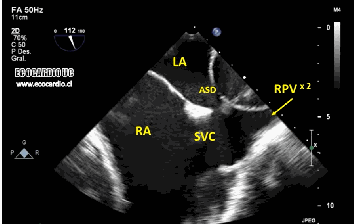

Bicaval view is an Important TEE view to visualize, the LA, IAS, and right atrium. I used to have some trouble getting oriented to this view. Hence this post. It is obtained in the 90-120 degree view at the mid esophageal position. Imagine the patient is lying on his left side and the probe comes from above down between the spine and heart to the LA from within the esophagus. This is the best view to see IAS in the profile.(Subcostal TTE can also do it) Note how the LA hugs the right atrium which is actually an ill-defined (In TEE I mean) common meeting point of both IVC and SVC. Also important is the relationship of RUPV with SVC & the horizontally running RPA sitting right over the top of LA.

The relationship between RUPV and SVC is crucial in device closure of large ASD, especially in sinus venous defect.

Very useful in ASD rim morphology especially in the posterosuperior rim.

Delineates clearly the defect boundaries in SVC ASD.

Sinus venosus defect: Image source not known. Thanks to the creator.